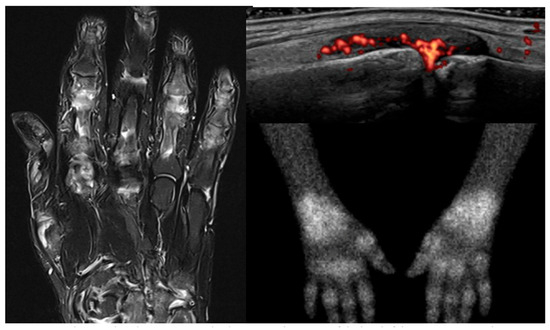

4. How Do Nuclear Imaging Techniques Compare to Conventional Imaging?